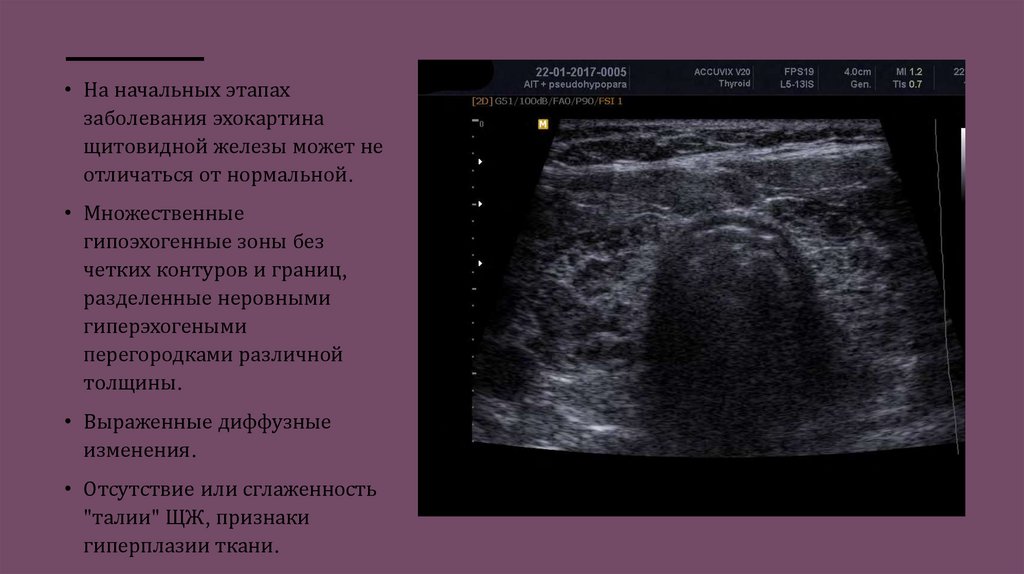

• На начальных этапах

заболевания эхокартина

щитовидной железы может не

отличаться от нормальной.

• Множественные

гипоэхогенные зоны без

четких контуров и границ,

разделенные неровными

гиперэхогеными

перегородками различной

толщины.

• Выраженные диффузные

изменения.

• Отсутствие или сглаженность

"талии" ЩЖ, признаки

гиперплазии ткани.